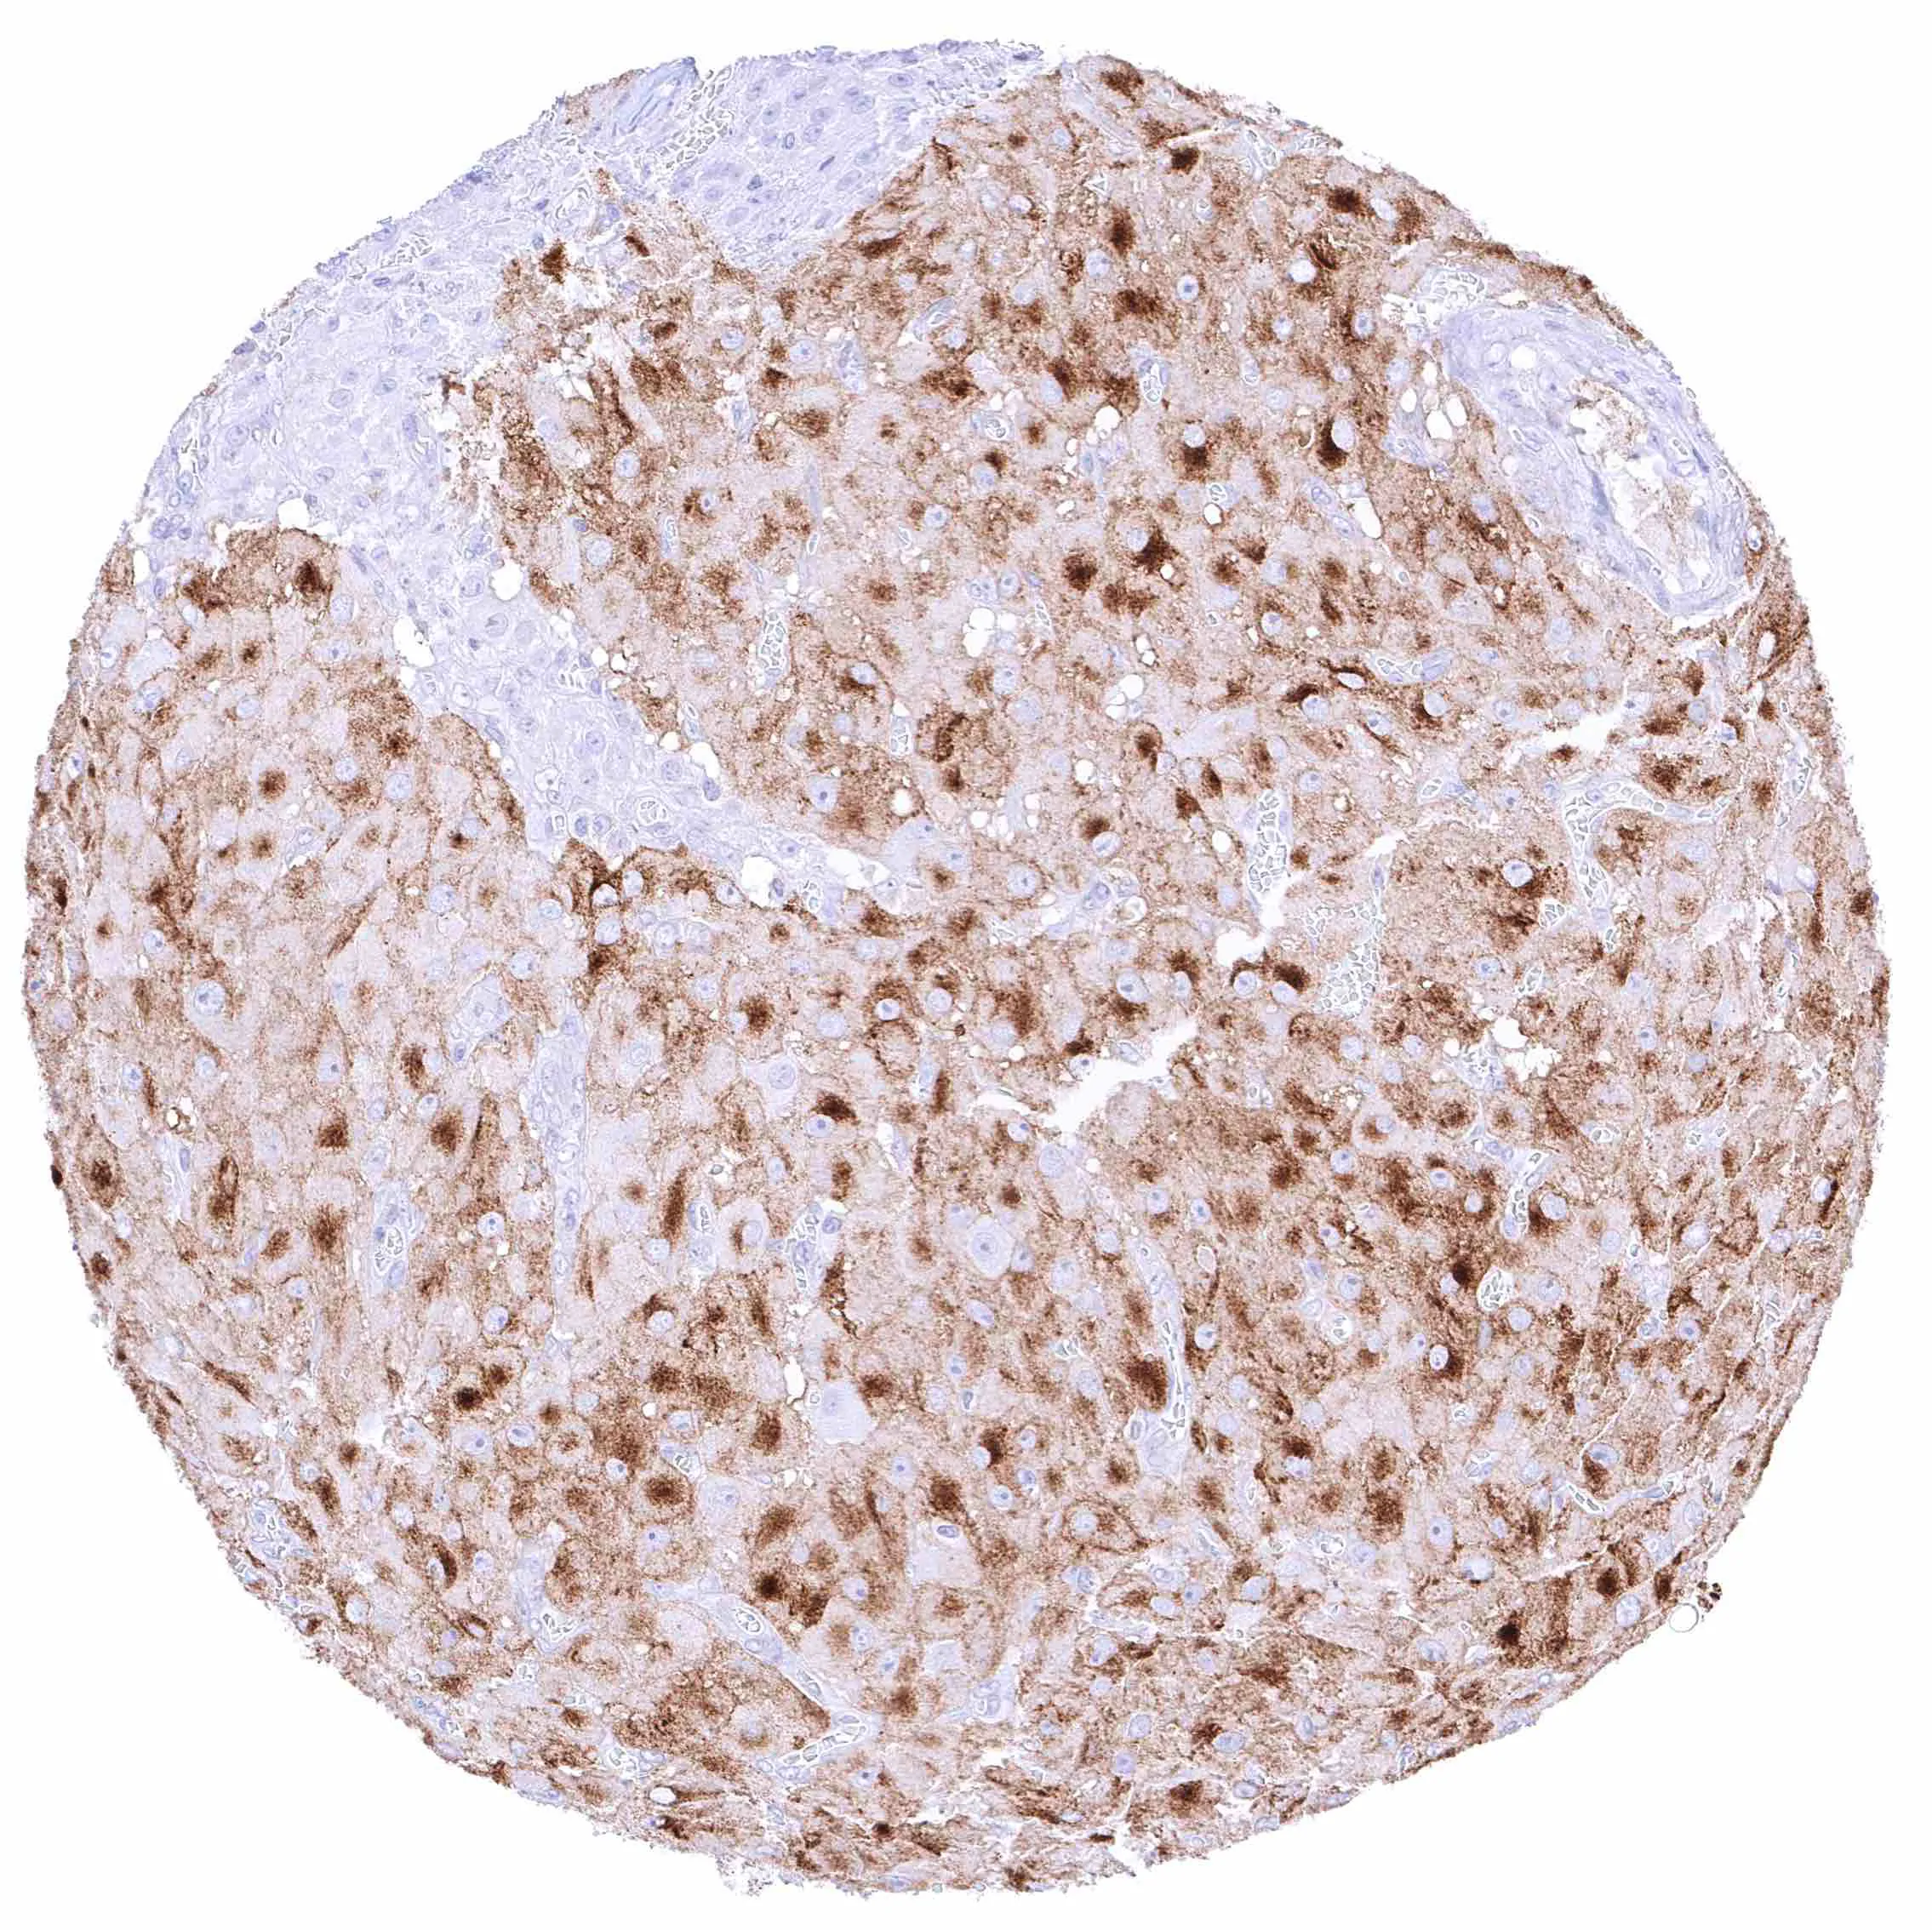

Seminal vesicle – Intense membranous NPR-C staining at the luminal cell border of endothelial cells of small blood vessels.